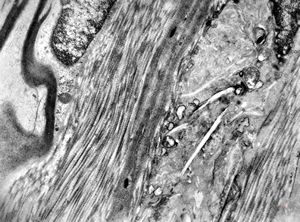

F,23y. | n.suralis - hypertrophic demyelinating neuropathy [onion bulb]

F,31y. | hypertrophic demyelinating neuropathy - n.suralis

M,13y. | n. suralis - hypertrophic demyelinating neuropathy